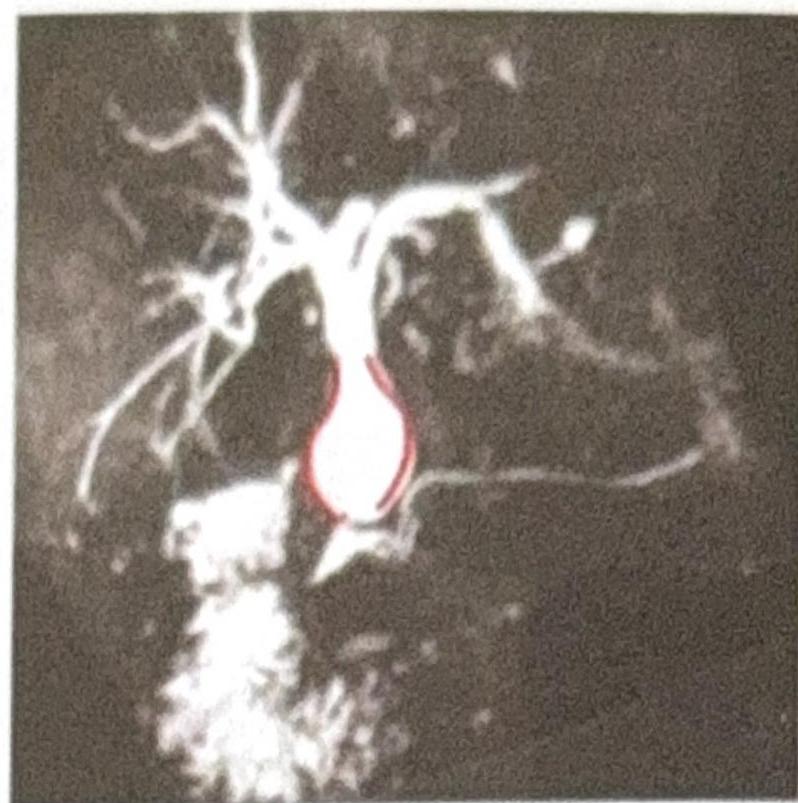

What condition does the MRCP (Magnetic Resonance Cholangiopancreatography) image indicate?

Explanation: **Choledochal cyst** - The MRCP image clearly shows a **cystic dilation** of the common bile duct, which is characteristic of a choledochal cyst. - This congenital anomaly involves saccular or fusiform dilation of the bile ducts, as depicted by the **balloon-like structure** in the image. - MRCP is the **gold standard imaging modality** for diagnosing choledochal cysts, providing excellent visualization of the biliary tree anatomy. *Dilated CBD (Common Bile Duct)* - While a choledochal cyst is a type of CBD dilation, simply stating "dilated CBD" is not specific enough, as the image shows a distinct **cystic morphology** beyond just uniform dilation. - Common bile duct dilation can be caused by various factors like stones or strictures, but the **focal, bulbous appearance** points specifically to a cyst. *Acute cholecystitis* - Acute cholecystitis typically presents with signs of gallbladder inflammation, such as **gallbladder wall thickening**, pericholecystic fluid, and gallstones, which are not depicted in this MRCP. - MRCP primarily visualizes the bile ducts and does not typically show the inflammatory changes of the gallbladder wall as clearly as ultrasound or CT. *Cholangiocarcinoma* - Cholangiocarcinoma usually manifests as a **stricture** or **mass** within the bile ducts, causing upstream dilation, rather than the isolated cystic dilation seen in the image. - There is no evidence of an obstructing mass or irregular narrowing within the bile ducts that would suggest a malignancy.